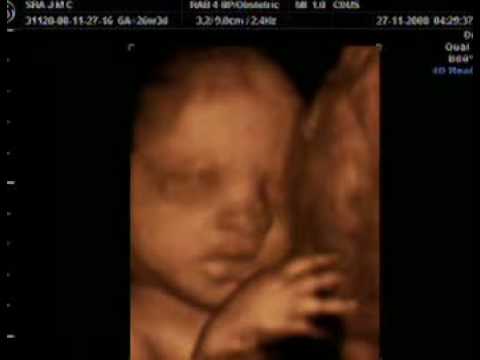

Neste vídeo dá pra ver o finalzinho do ultra-som da 26ª semana. Isso porque ainda não conseguimos ripar tudo para extrair as partes mais interessantes, pois estão ocorrendo alguns erros estranhos, coisas da informática :-)

Mas o que importa aqui é que o médico deu uma palhinha de como vai ser o ultra-som 4D que faremos em breve. Deu pra ver o rostinho dela pela primeira vez!!! Segundo a Junia, ela se parece comigo. Mas eu acho que o queixinho parece com o dela!